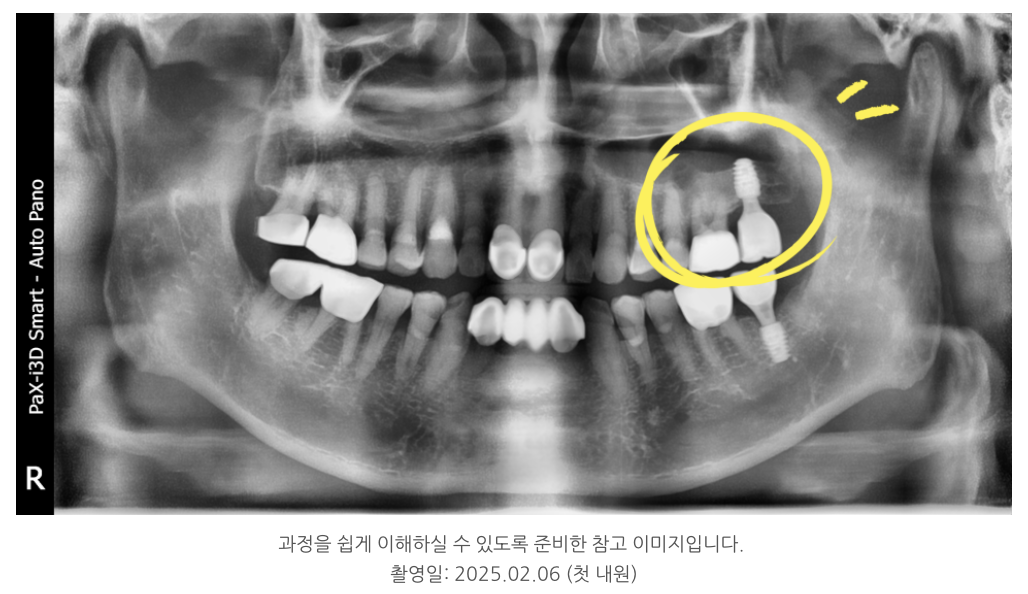

얼마 전 70대 남성 환자분이

“임플란트가 흔들린다”는 불편감으로 내원하셨습니다.

겉보기에는 단순히 고정력이 떨어진 것 같았지만,

환자분은 동시에 뺨이 무겁게 당기는 느낌과 코막힘을 호소하고 계셨습니다.

대부분 환절기마다 나타나는 증상이라 대수롭지 않게 여기셨지만,

정밀 검사를 통해 원인을 확인해보니 문제는

임플란트 자체가 아니라 상악동염이었습니다.